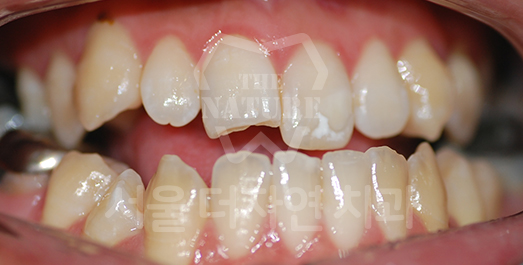

Crowding (Supernumerary / Overlapping Teeth) Solution

Crowding occurs when there is insufficient space for teeth to erupt into proper position.

If left untreated for a prolonged period, inadequate brushing access leads to food impaction between teeth

and a significantly elevated risk of dental caries.

As crowding is also a contributing factor to periodontal disease,

orthodontic correction is strongly recommended.

BEFORE: 2020.06.11

AFTER: 2023.02.02